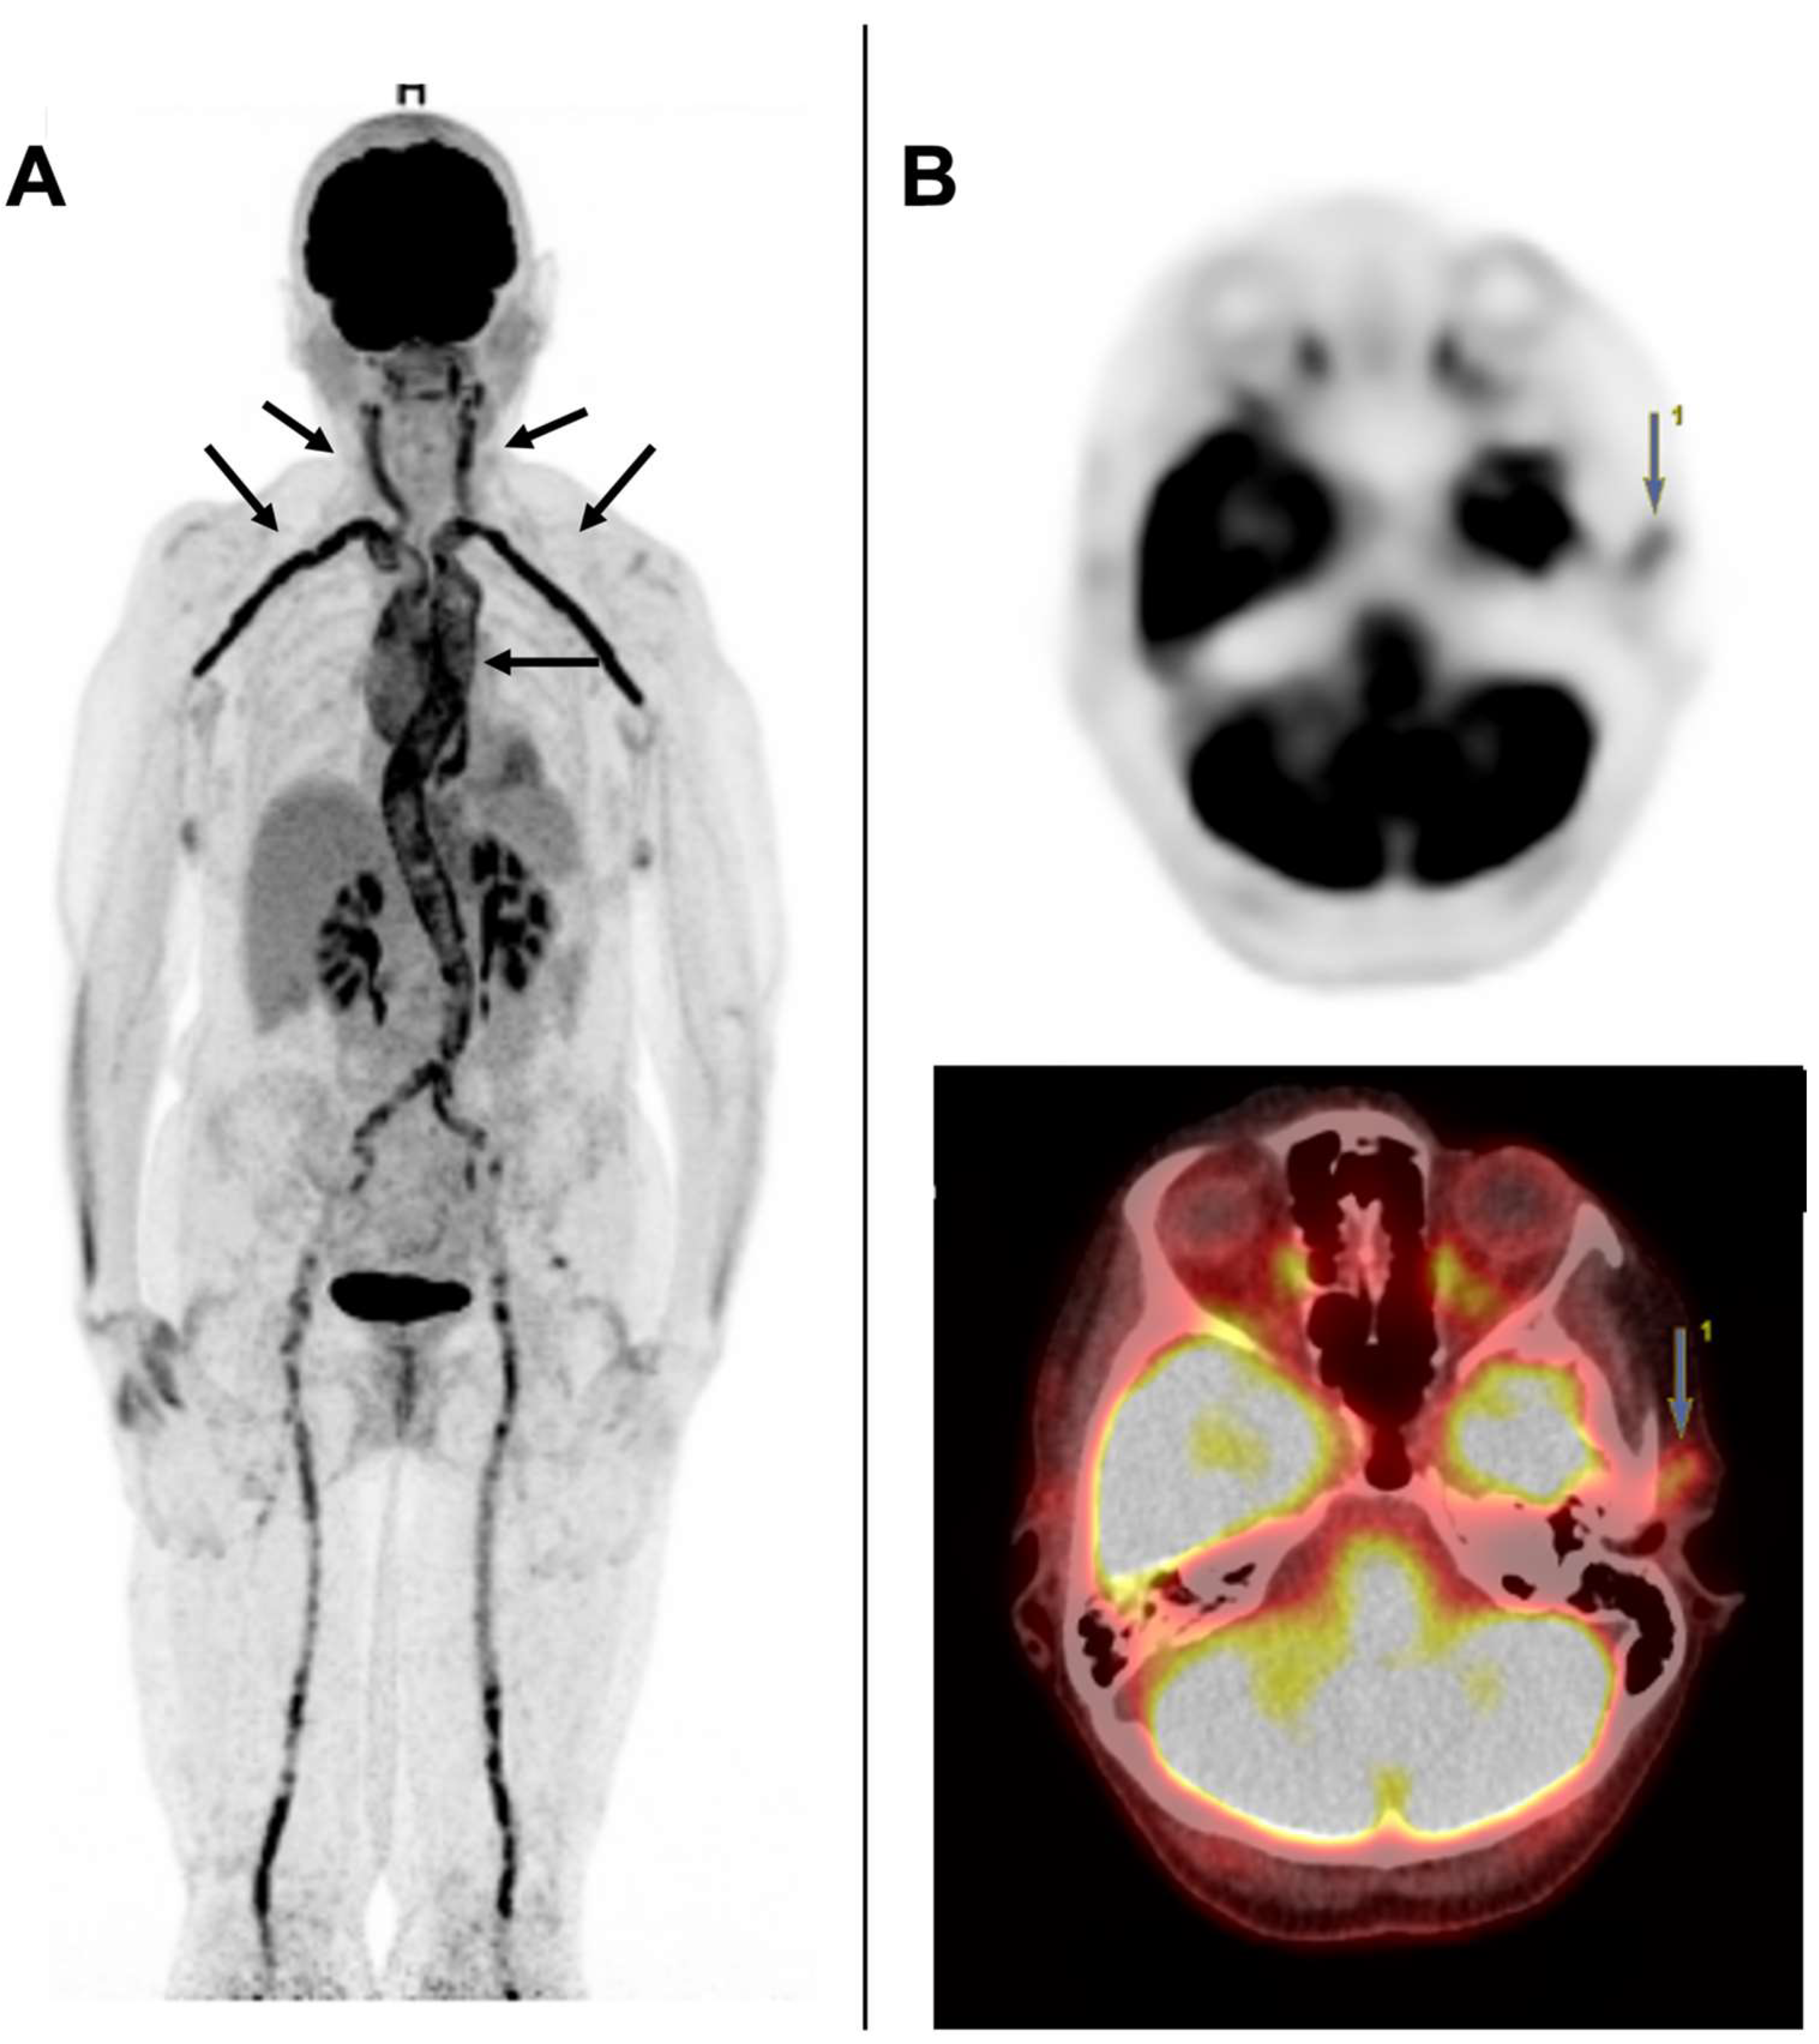

5.2. [18F] FDG-PET/CT

- Thibault, T.; Durand-Bailloud, B.; Soudry-Faure, A.; Greigert, H.; Drouet, C.; Devilliers, H.; Ramon, A.; Bejot, Y.; Martin, L.; Creuzot-Garcher, C.; et al. PET/CT of Cranial Arteries for a Sensitive Diagnosis of Giant Cell Arteritis. Rheumatology 2022. online ahead of print. [Google Scholar] [CrossRef]

- Sammel, A.M.; Hsiao, E.; Schembri, G.; Nguyen, K.; Brewer, J.; Schrieber, L.; Janssen, B.; Youssef, P.; Fraser, C.; Bailey, E.; et al. Diagnostic Accuracy of Positron Emission Tomography/Computed Tomography of the Head, Neck, and Chest for Giant Cell Arteritis: A Prospective, Double-Blind, Cross-Sectional Study. Arthritis Rheumatol. 2019, 71, 1319–1328. [Google Scholar] [CrossRef]

- Nielsen, B.D.; Hansen, I.T.; Kramer, S.; Haraldsen, A.; Hjorthaug, K.; Bogsrud, T.V.; Ejlersen, J.A.; Stolle, L.B.; Keller, K.K.; Therkildsen, P.; et al. Simple Dichotomous Assessment of Cranial Artery Inflammation by Conventional 18F-FDG PET/CT Shows High Accuracy for the Diagnosis of Giant Cell Arteritis: A case-control study. Eur. J. Nucl. Med. Mol. Imaging 2019, 46, 184–193. [Google Scholar] [CrossRef]